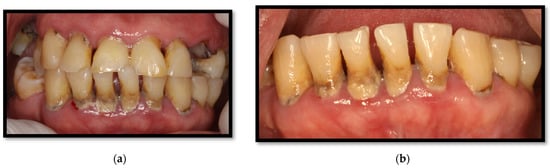

3. Periodontal Disease

3.1. Linear Gingival Erythema

3.2. Periodontitis

3.3. Necrotizing Gingivitis (NG)

3.4. Necrotizing Periodontitis (NP)